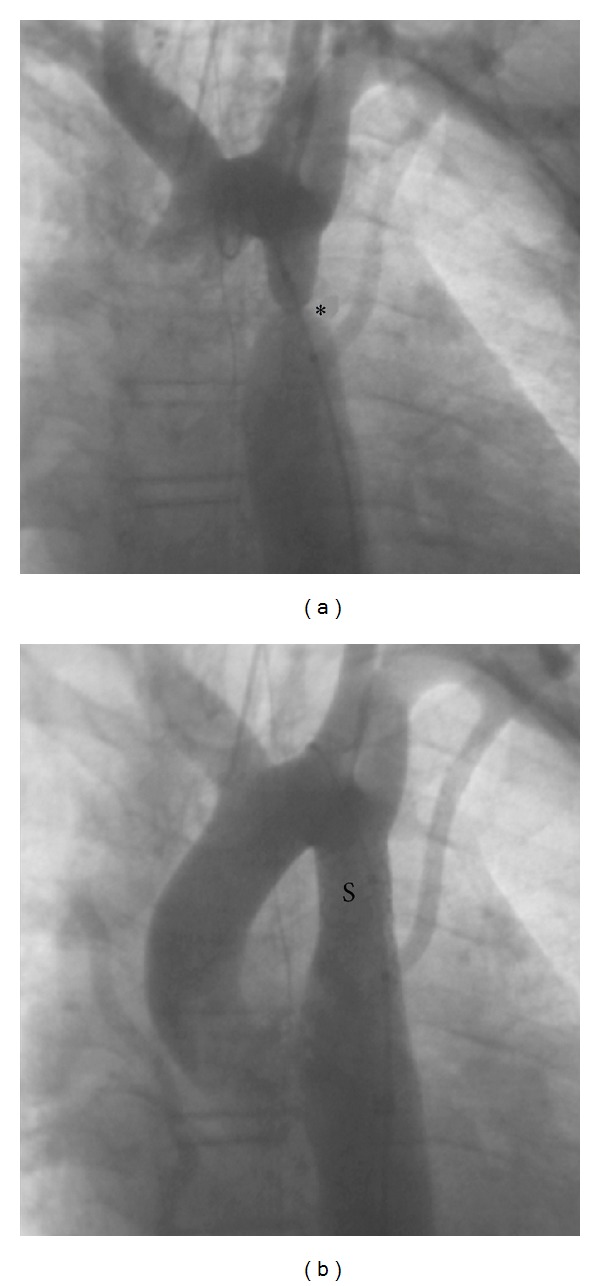

In older children, stenting of coarctation is very simple as the narrowing can be easily accessed and stented with bare metal stents from the femoral artery (Figure 1). Stenting in newborns and smaller children (<15 kg) can often be more technically challenging, but it is still able to be performed at relatively low risk to the patient, though surgery remains the gold standard due to the requirement that current BMS will need to be redilated at least 3x their initial implantation size to reach adult size as the child grows. Thus, stenting for coarctation in infants and smaller children is only performed as palliation in children deemed too sick for surgical intervention (Figure 2).

Figure 1.

Coarctation (∗) before (a) and after (b) stent (S) placement. This procedure performed by our team provided complete resolution of this severe aortic stenosis.